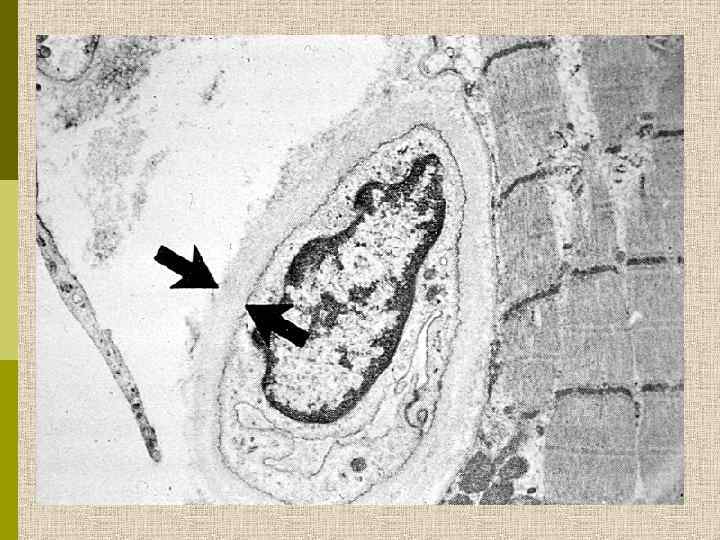

Диабетическая микроангиопатия/утолщение базальной мембраны 1. Образование аневризм 2. Утолщение базальной мембраны 3. Leakyсосуды и базальные мембраны

МОРФОЛОГИЧЕСКИЕ ИЗМЕНЕНИЯ ПРИ ДИАБЕТИЧЕСКОЙ НЕФРОПАТИИ Основные варианты - диабетический гломерулосклероз с узелками Kimmelstiel-Wilson - диффузный мезангиальный гломерулосклероз Характерные признаки Утолщение ГБМ; артериолярный гиалиноз; аневризматические капилляры; капсулярные капли; фибриновые шапочки; атрофия канальцев; инфильтрация, расширение и склероз интерстиция; линейные отложения иммуноглобулинов